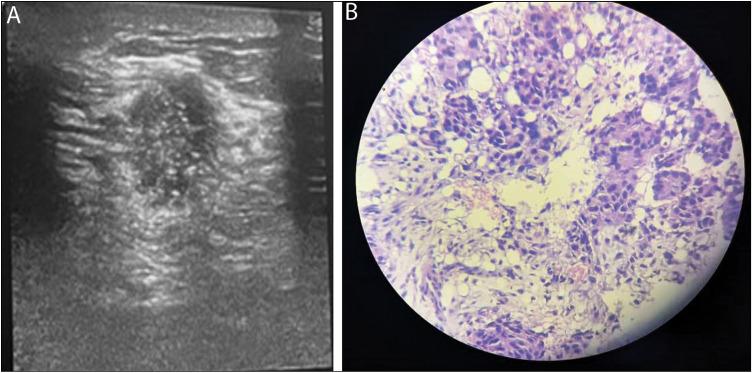

Following recommended guidelines, palpable breast lumps in young women should be subjected to clinical-radiologic evaluation and tissue diagnosis where necessary. However, in our local practice, most benign breast lumps are also subjected to excision biopsy. Ultrasonography is the modality of choice in the evaluation of palpable breast lumps in young women.

This study aims to determine the accuracy of ultrasonography and the necessity of tissue biopsy in the management of palpable breast lumps in women less than 40 years of age and to determine lesions that can safely be managed conservatively based on histological diagnosis.

This was a prospective cross-sectional study of 87 adult females who had breast US and biopsy for palpable breast lumps in a tertiary healthcare center over a period of 10 months (July 2020-May 2021).

The age range of the women was 18-39 years (mean 27.9 ± 7.09 years).Benign lesions were noted in 86.2% of patients. No malignancy was detected in women < 25 years. Ultrasonography had sensitivity, specificity, positive predictive value, negative predictive value, and accuracy of 100%, 93.4%, 70.6%, 100%, and 94.3%, respectively, in differentiating benign from malignant breast lumps following tissue diagnosis.

Ultrasonography and tissue biopsy are vital in the evaluation of breast lumps in women less than 40 years of age. Most (86.2%) of the lumps were benign, and no malignancy was detected in women < 25 years. The high accuracy of ultrasonography in distinguishing benign from malignant lesions suggests the need for conservative management of benign lumps in young women.